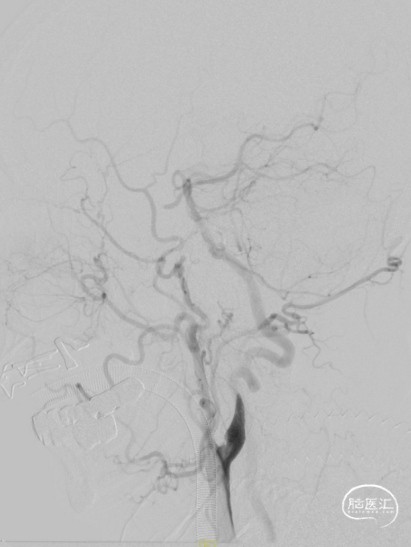

手推冒烟见RICA C1-C5段显影,C5段以远闭塞。将Pro-18微导管在Synchro(0.014×200mm)微导丝引导下送至RMCA M2段,微导管冒烟示远端血流通畅。将Trevo XP(4×20mm)取栓支架于M1段远端向RICA末端释放,采用SWIM技术取栓1次,并同时将中间导管送至颈内动脉末端抽吸。抽出数枚暗红色血栓。

造影见RICA再通,RMCA M1段近端重度狭窄,约90%。

观察10分钟后,狭窄较前加重,局部不规则充盈缺损。术中即刻DynaCT未见造影剂染色。